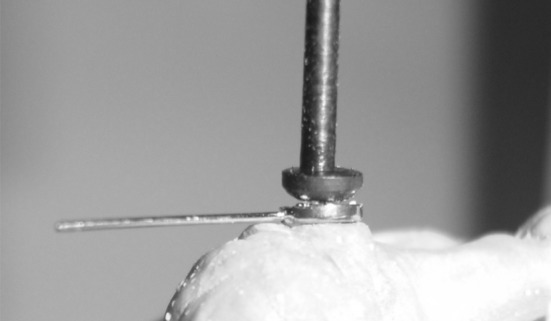

Abutment teeth (32,33,34 and 43) were prepared with diamond rotatory instruments (Shofu, Kyoto, Japan), producing a chamfer margin and decoronated slightly above the gingival margin followed by removal of two-third of the root canal filling material with a stainless rotary instrument (Peasow reamer; Dentsply, York, Pa) to prepare the post space to accommodate post along with keeper (Fig. 2). Cervical portion of all the abutment teeth were marginally bevelled to prevent any stress concentration eventually to prevent root fracture.

Fig. 2.

Post space preparations, gingival retraction and impressions of posts